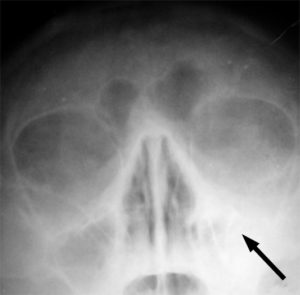

Legen kan ta blodprøve, røntgenbilde, sjekke om slimhinnen er hoven og om det er væske i bihulene dersom han finner det nødvendig.

Røntgen kan være aktuelt i noen tilfeller. Bilde: wikipedia.no